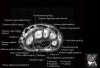

- Axial section

Axial T1 evaluates the tendons of the wrist and carpal tunnel, including the flexor retinaculum.